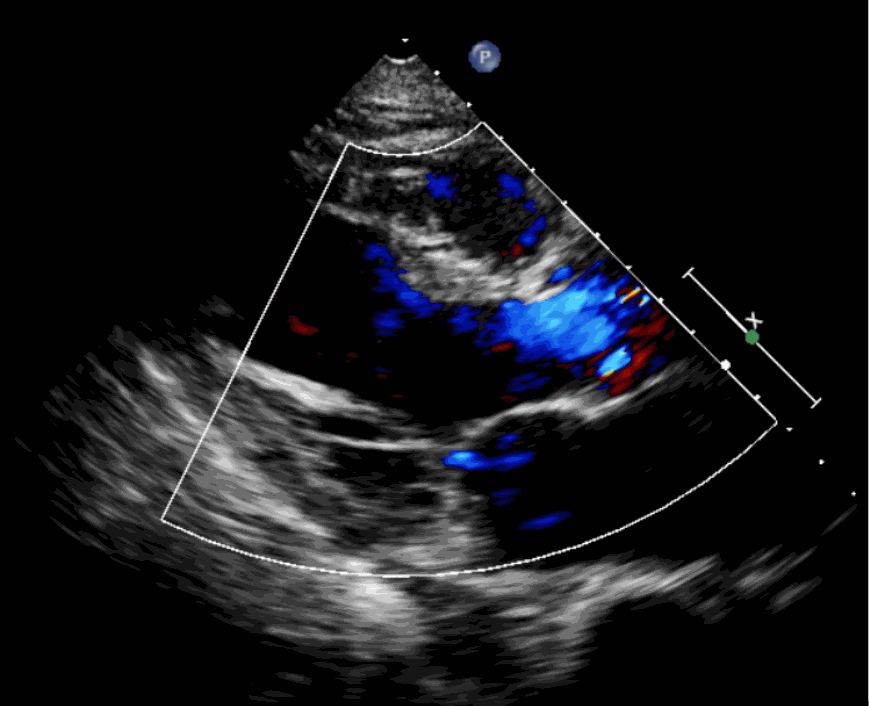

術(shù)前超聲影像圖

該例患者為62歲,女性,因“間歇性心悸、胸悶、氣短、胸痛1年,加重1周”之主訴入院。入院診斷:主動脈瓣重度關(guān)閉不全,二尖瓣、三尖瓣輕度關(guān)閉不全,心功能III級;冠狀動脈粥樣硬化性心臟病。行心臟超聲心動圖提示“主動脈瓣重度關(guān)閉不全;瓣口水平以下左室下壁、后下壁搏幅減低;EF值 0.30,左房、左室大、右房大小正常高限;二尖瓣、三尖瓣關(guān)閉不全;輕度肺動脈高壓(收縮壓42mmHg);主動脈硬化;左室收縮功能重度減低。經(jīng)心血管外科劉洋、楊劍教授、麻醉科陳敏教授及超聲科孟欣教授等專家團隊綜合評估,判定患者為外科手術(shù)高危患者。